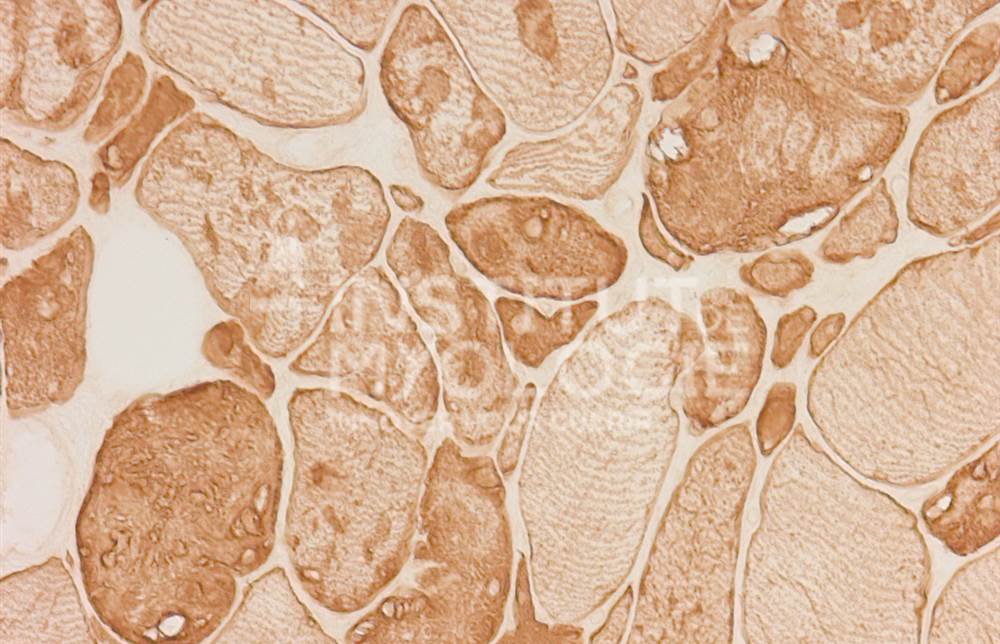

Welcome to the Muscle Atlas, the first database of muscle images designed to facilitate research, diagnosis and knowledge in the field of neuromuscular pathologies. Our vast collection includes more than 6,416 images of muscle biopsies from patients with various diseases and animal models, which may or may not be undergoing treatment. Each image is characterised according to the specific condition and corresponding stage of the disease.